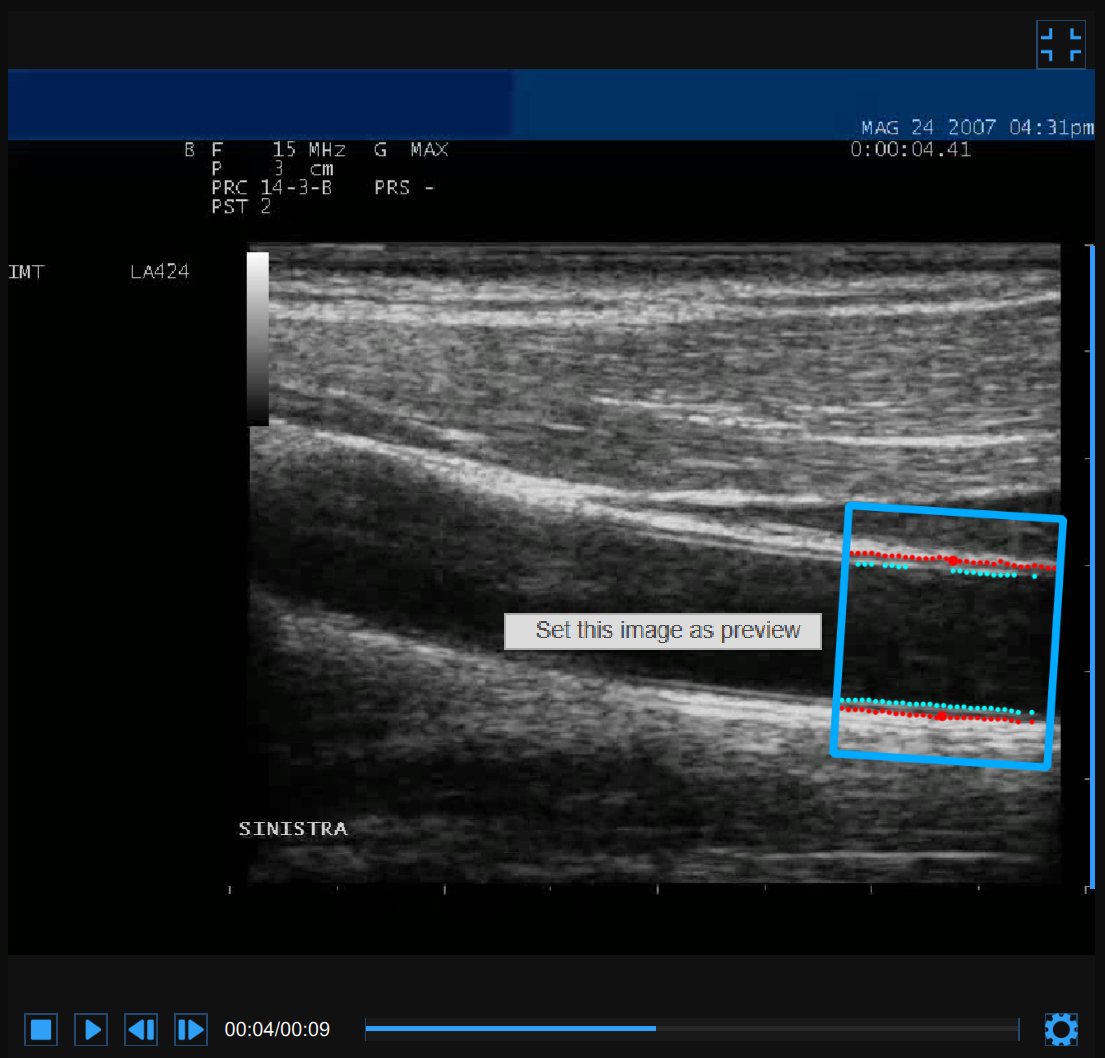

Video window

The video window shows the video signal from your ultrasound system. The points of the Lumen-Intima interface and the Media-Adventitia interface are displayed within the ROI (2) in cyan color.

The video control bar (1) is located at the bottom of the window.

If you perform right click on the video window and click on "Set this image as preview" the current frame will be saved and displayed in the Documents Table as document preview (see Studies management).